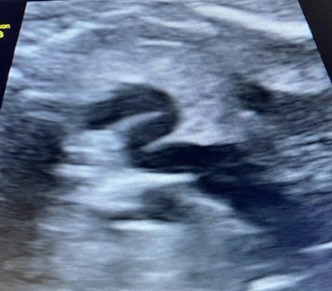

This concerns a 27 year old woman, feat 2, birth 0, abortion 1, with no significant medical history, currently at 35+5 weeks of gestation under obstetric care. She was referred to the fetal exploration unit due to suspicion of fetal cardiac malformation and tricuspid regurgitation. The fetal echocardiogram showed a structurally normal heart with mild tricuspid regurgitation, and no signs of heart failure were detected. Both ventricles exhibited good function. A dilated ductus arteriosus with an "S" shape measuring 10mm in length was observed, with a pulmonary end diameter of 3.2mm and an aortic origin diameter of 3mm (Figure 1 & 2). Ductal velocity was measured at 160cm/s. At the 37+6 weeks’ gestation evaluation, no significant changes were found compared to the previous fetal echocardiogram, with normal umbilical Doppler. The mother had a history of taking paracetamol at 29 weeks of gestation, every 8 hours for two days, due to a viral illness.

Figure 1 Dilated and tortuous “S” shaped ductus arteriosus in fetus of 35+5 gestational weeks.